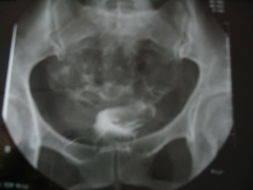

1、输精管造影检查。查看患者无精症是不是属于输精管堵塞问题。该检查是将造影剂通过切开法或经皮穿刺法注入输精管,使其显示输精管、精囊及射精管等组织结构,以了解输精管是否通畅,精囊腺有无病理变化等,明确引起男性不育的病因。